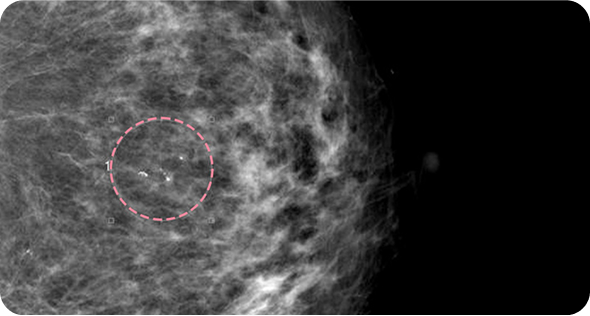

유방 양성 종양은 한 개만 나타나는 것이 아니라

동시다발적으로 생겨나기도 합니다.

여러 개의 양성 종양 제거는 정상적인 유방 조직을 온전히

보전할 수 있도록 섬세한 시술이 필요합니다.

한송이 원장은 다발성 종양 제거에 대한 풍부한 경험을 토대로,

무리 없이 맘모톰 조직검사 및 제거를 진행했습니다.

맘모톰시술 6개월 후 유방초음파 검사 시행 결과 종양이 깨끗하게 제거됨을 확인했으며, 약간의 반흔 조직이 남았으나 시간이 지나면서 대부분 사라지기 때문에 좋은 예후가 기대되었습니다.